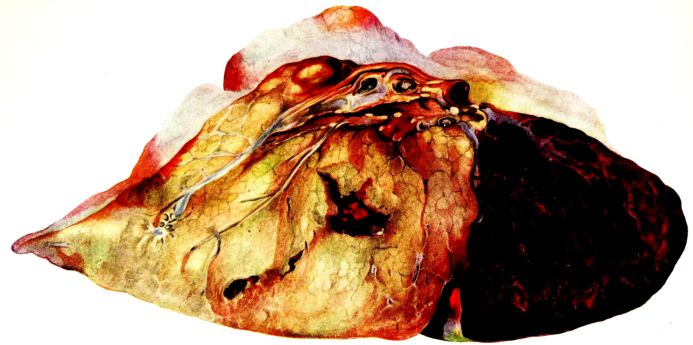

FIG. I. AUTOPSY NO. 99. ACUTE HEMORRHAGIC AND ULCERATIVE LARYNGOTRACHEITIS.

FIG. I. AUTOPSY NO. 99. ACUTE HEMORRHAGIC AND ULCERATIVE LARYNGOTRACHEITIS.

Early in the disease the congestion and the hemorrhages that have been described in the mucous membrane of the nasopharynx (14 and 94) are also conspicuous features in the lining of the trachea and bronchi (Fig. I). This membrane is swollen, turgid, red, and covered by a copious, mucous exudate which may be clear, but much more frequently is blood-stained or opaque and yellowish in color. The blood, variable in amount, may be fresh and red; and after the mucous exudate on the surface is removed, more intense red foci stand out on the congested base (47, 90, 157). Frequently, as the bronchi are approached, the red color of the mucosa becomes more intense and may have a garnet tinge. Membranes such as are encountered in the more usual necrotizing inflammatory processes, like diphtheria, have not occurred in the trachea and larger bronchi in this series (108, 128, 157).[3] The exudate peels off readily, and as indicated above, leaves a velvety red surface, 14dotted here and there with darker or more intensely red foci. Small ulcerations of the mucosa occur, but are inconspicuous (82, 156). As the finer ramifications of the bronchi are approached, the accumulation of the exudate in their lumina becomes more and more marked, and on cross section of the lung, they often stand out conspicuously on account of their increased size and projecting, seromucous, blood-stained content (101, 149, 162).